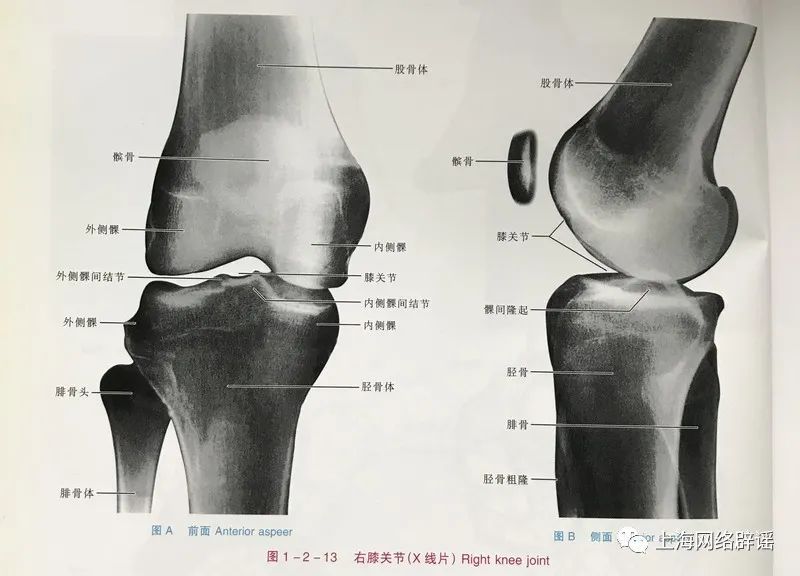

膝关节结构复杂,按摩仪恐很难保证其宣传的效果。

上海体育学院运动科学学院副教授郭黎也表示,膝关节是人体的关键承重关节,也是人体内最复杂的关节。肌肉的控制力直接影响膝盖的承受力,只有腿部肌肉发达,才能强有力地支撑膝关节,帮助膝关节分担运动时产生的冲击力。如果感到膝关节力量不足,可以进行靠墙半蹲或箭步蹲练习,以提高腿部肌肉力量,特别是膝关节周边的肌肉力量。